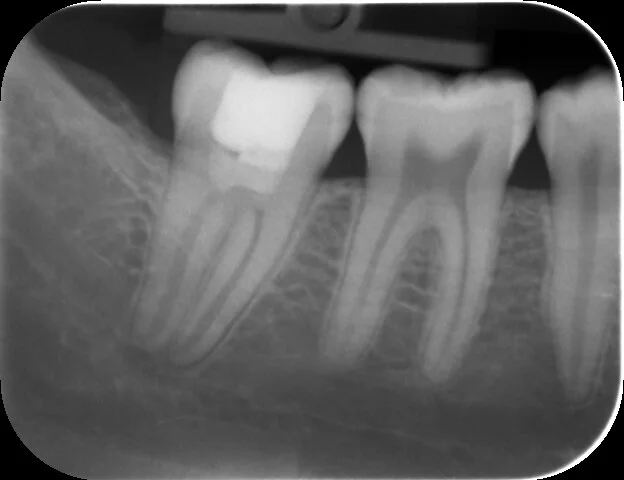

A fourteen year old was referred to me as they were experiencing pain from the lower right side. The periapical radiograph shows a deep carious lesion on the mandibular second molar that has breached the mesial pulp horn. It is also clear that there is incomplete root development.

When I saw the patient I did a vitality test for this tooth which confirmed my suspicion that the tooth was still vital. This information decided the treatment, a vital pulp therapy.

Two years and no symptoms later a review radiograph shows continued root development on the mandibular second molar.